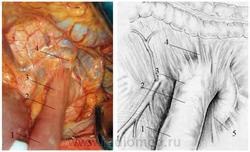

Рисунок 2.5. Укорочение и высокая фиксация связки Трейтца (интраоперационное фото – слева, схема - справа.)

1 – первая петля тощей кишки; 2 – дуоденоеюнальный переход; 3 – связка Трейтца; 4 – поперечно-ободочная кишка; 5 – восходящая часть ДПК.